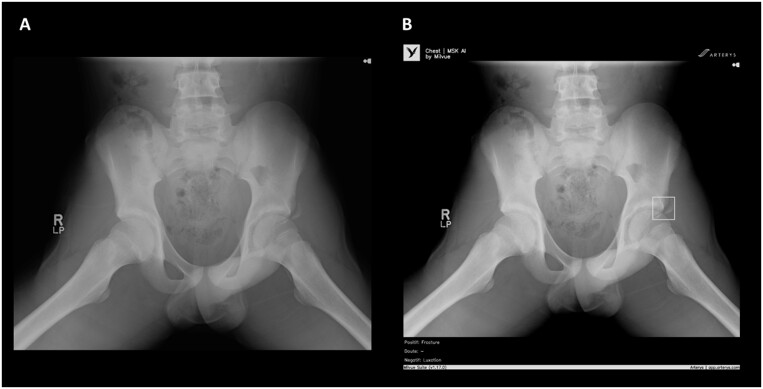

Abstract Image